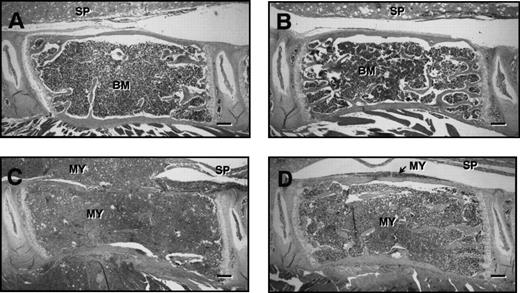

Figure 5 shows representative histological sections of lumbar vertebrae from control and myeloma-bearing mice treated with PBS or ibandronate. In myeloma-bearing mice treated with PBS (Fig 5C) a reduction in trabecular bone as well as occasional thinning and destruction of cortical bone was observed when compared with non–tumor-bearing control mice (Fig 5A and B). This loss of bone was prevented by treatment with ibandronate in myeloma-bearing animals (Fig 5D). Histomorphometric analysis confirmed that mean values for trabecular bone volume in the vertebrae of 5TGM1 myeloma-bearing mice treated with PBS were significantly lower than those in non–tumor-bearing controls (see Table 1). This reduction in bone volume was prevented by treatment with ibandronate. Mean values for trabecular bone volume in the vertebrae of both control and tumor-bearing animals treated with ibandronate were higher than those in the PBS-treated controls, but these differences failed to reach statistical significance.

Fig. 5.

H & E stained sections of lumbar vertebrae from control and 5TGM1 myeloma-bearing mice treated with PBS or ibandronate (4 μg per mouse per day for 28 days). (A) Non–tumor-bearing control treated with PBS, (B) non–tumor-bearing control treated with ibandronate, (C) 5TGM1 myeloma-bearing mouse treated with PBS, (D) 5TGM1 myeloma-bearing mouse treated with ibandronate. The spinal cord (SP) is indicated in each figure. Note that in the non–tumor-bearing animals, (A) and (B), the marrow cavity is filled with normal marrow (BM). In contrast in myeloma-bearing animals (C) and (D), the normal bone marrow has been replaced by myeloma cells (MY), which have also invaded the surrounding tissues. In the myeloma-bearing animal treated with PBS (C), there is a clear loss of trabecular bone and also some loss of cortical bone. This bone loss is prevented by ibandronate treatment (D). Bar = 200 μm.